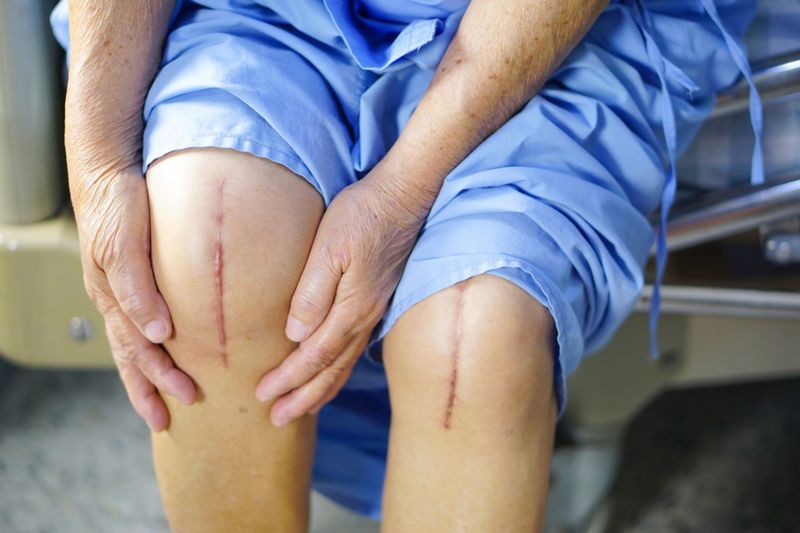

5. Happy Feet Program:

It is a pathbreaking program for children and young adults with difficulty in walking due to the disorders of lower limb. Some children with gait disorders will benefit from corrective surgery. A host of disorders across cerebral palsy, club foot and developmental dysplasia’s apart from many other deformities will be treated under this program.